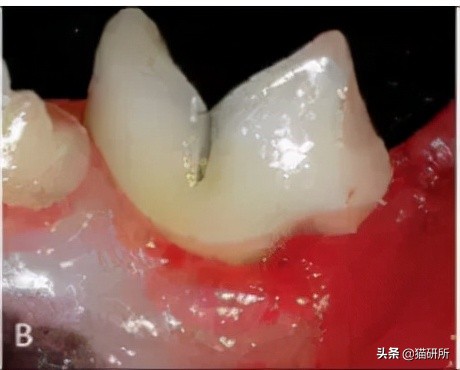

牙龈炎 (A)、牙周炎 (B) 牙周炎会出现牙龈萎缩,齿根暴露 图自:researchgate